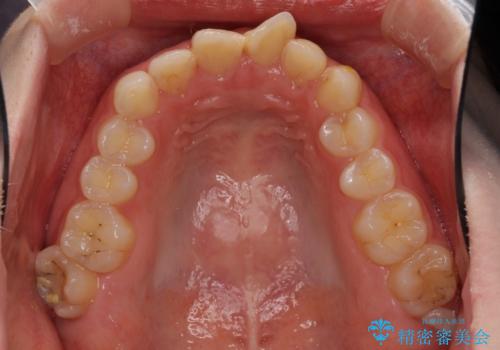

- 前歯の歯並びと虫歯を気にして来院された患者様です。

上下前歯の歯列不正はインビザラインにより歯列を整え、その後に、前歯5本をオールセラミッククラウンにて補綴治療することとしました。

矯正治療前に前歯のむし歯治療を行ったものの、樹脂で充填するには虫歯が広範囲であったため、審美的に問題がありました。